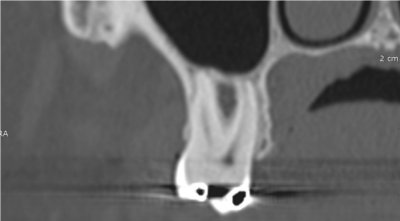

Le cone beam utilisé en pathologie dentaire et maxillo-faciale est indiqué pour l’examen des tissus minéralisés (dents, cartilages, os), il permet d’identifier les lésions osseuses, les fractures, les infections, les kystes ou les corps étrangers.

Ostéonécrose de la mandibule

- pathologies osseuses des maxillaires